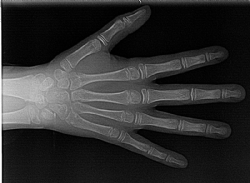

Handwurzelröntgen

Für kieferorthopädische Behandlungen ist es notwendig zu wissen, wie viel Kieferwachstum des Patienten noch erwartet werden kann. In wenigen Fällen ist eine exakte Beurteilung des Wachstumsstadiums erforderlich, was am besten anhand bestimmter Wachstumsfugen des Handskeletts erfolgt.